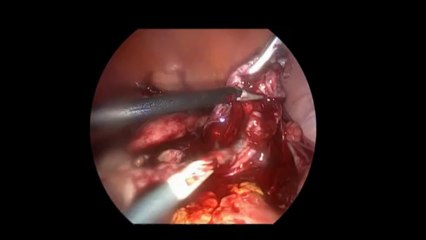

Laparoskopi ile Endometiroma (Çikolata kisti) operasyonu 1 - Prof. Dr. Aydan Biri

Laparoskopi ile Endometiroma (Çikolata kisti) operasyonu 1 - Prof. Dr.